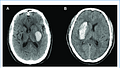

xuất huyết não

intracranial hemorrhage

Xuất huyết não là một loại đột quỵ, xảy ra khi máu tràn vào mô não và gây tổn thương não.